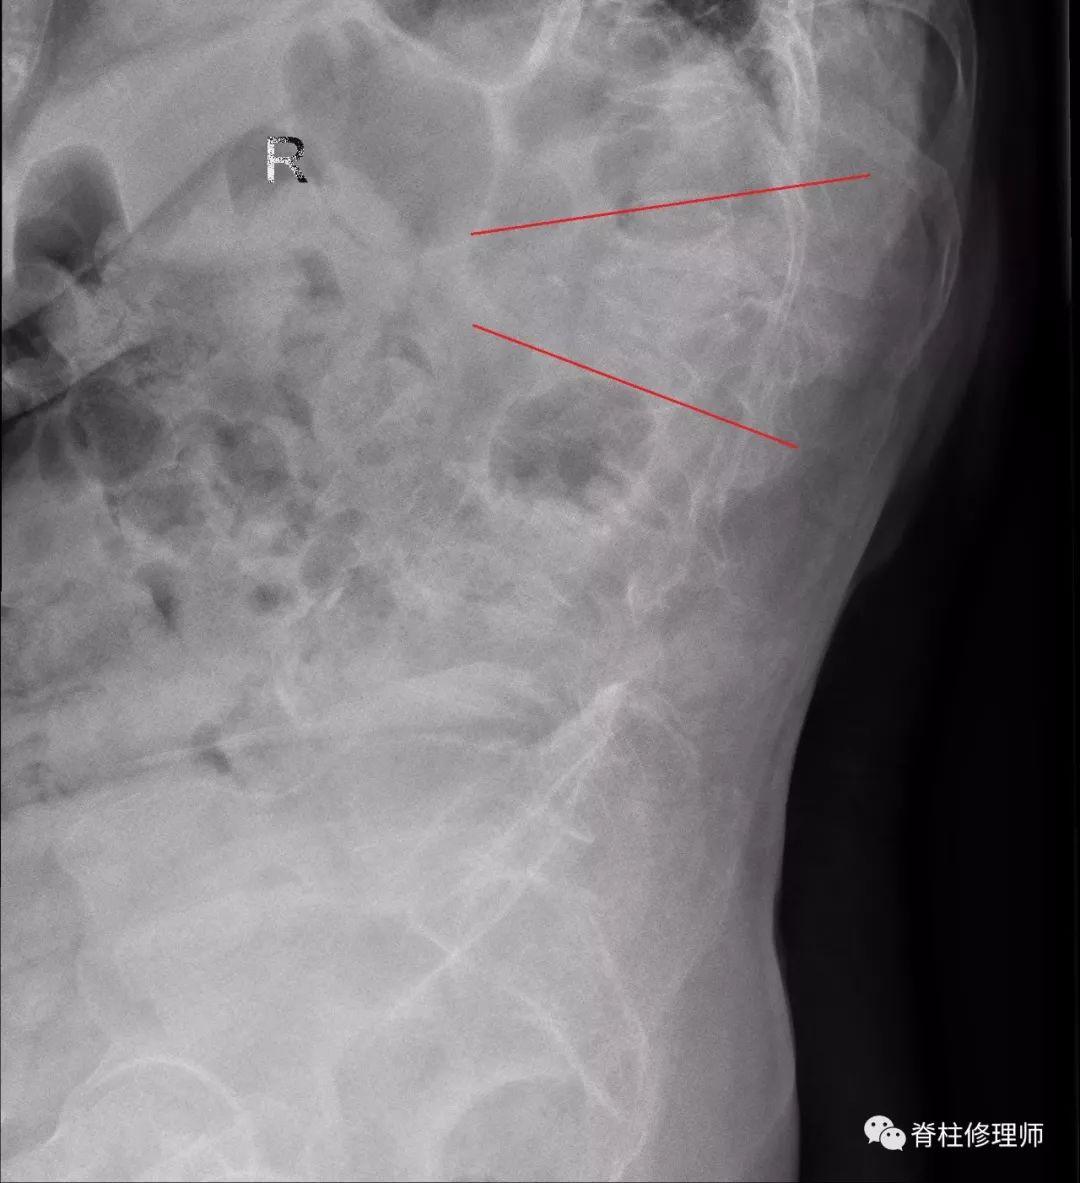

老年人常常因为没有受到外伤,发生骨折后仍不知情况,觉得腰背部不适只是衰老的表现,强忍疼痛。在椎体骨折后没有得到固定及休息,导致骨折愈合缓慢,甚至逐渐不愈合,也有发生轻微骨折不知情况后逐渐形成椎体的变形,发生kumells病。

罗湖中医院(上海中医药大学深圳医院)脊柱骨科近期就收到一位发生骨折的患者保守治疗后骨折无法愈合,发生kumells病。

对于kumells病,后凸畸形明显的患者需要行矫形手术,对于年龄较大的患者,这无疑是一道难关。